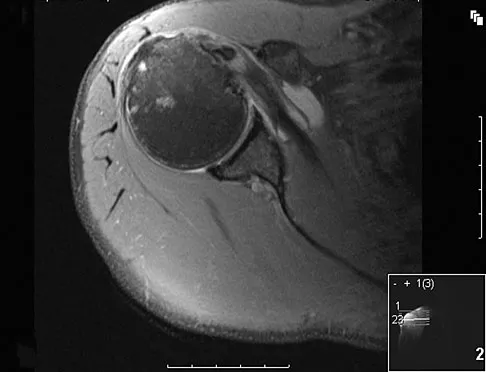

A 38-year-old left hand-dominant bodybuilder reports ecchymosis in the left axilla and anterior brachium after sustaining an injury while bench pressing 3 weeks ago. Coronal and axial MRI scans are shown in Figures 16a and 16b. What treatment method yields the best long-term results?